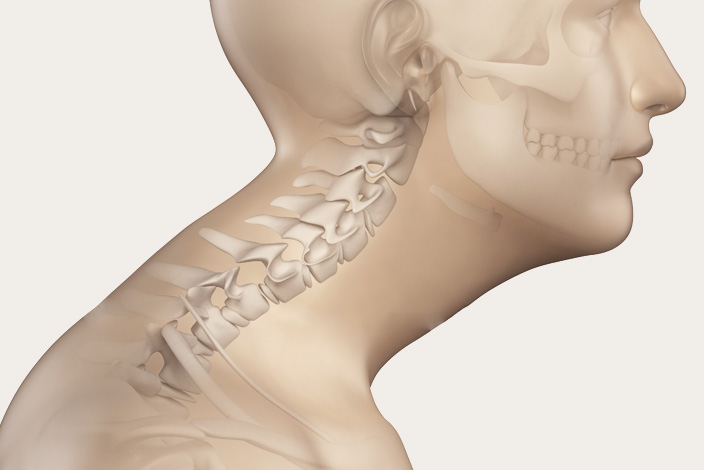

부적절한 자세

오랜 세월 그릇된 자세를 지탱하면 목에 무리가 가고 디스크 문제가 일어날 수 있습니다.

구부정하게 앉거나, 전자기기를 구부정하게 사용한 경우 혹은, 부적절한 자세로 오랜 시간 앉아 있는 등의 활동은 목 디스크에 심한 스트레스를 줄 수 있습니다. 이로 인하여 비정상적인 마모, 디스크 탈출 또는 신경 충돌이 생겨날 수 있습니다.